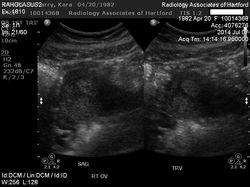

![]() Insemination | ![]() EggIn the middle in the right hand side there is a bright oval, that is the egg inside the uterus - can you spot it? | ![]() My Excited Sister |